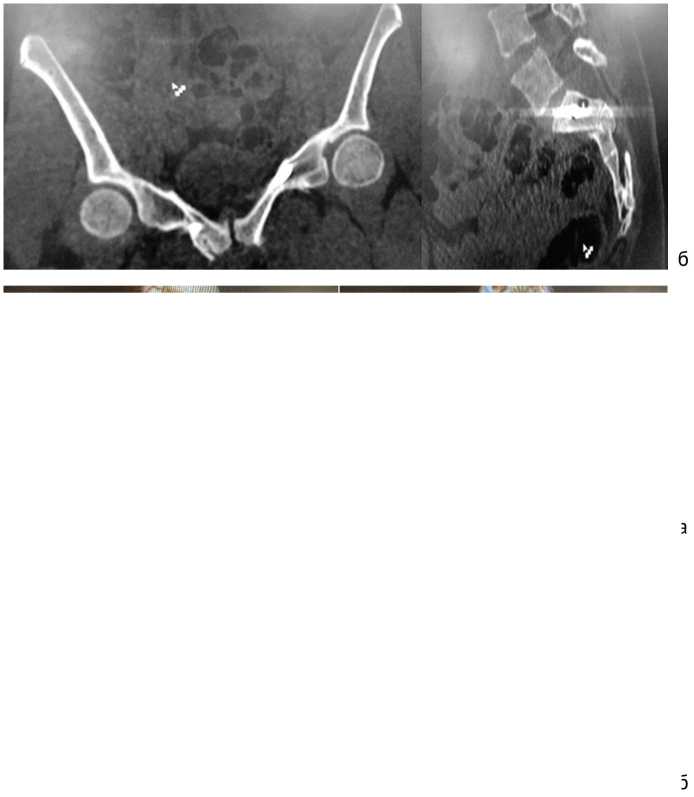

В результате КТ таза при поступлении выявлены: оскольчатый нестабильный перелом крестца со смещением; переломы правой лонной, седалищных костей и левой вертлужной впадины со смещением (рис. 1).

Рис. 1. Компьютерные томограммы таза пациентки при поступлении в стационар: а — 3D-реконструкции; б — сканы в аксиальной и сагиттальной проекциях